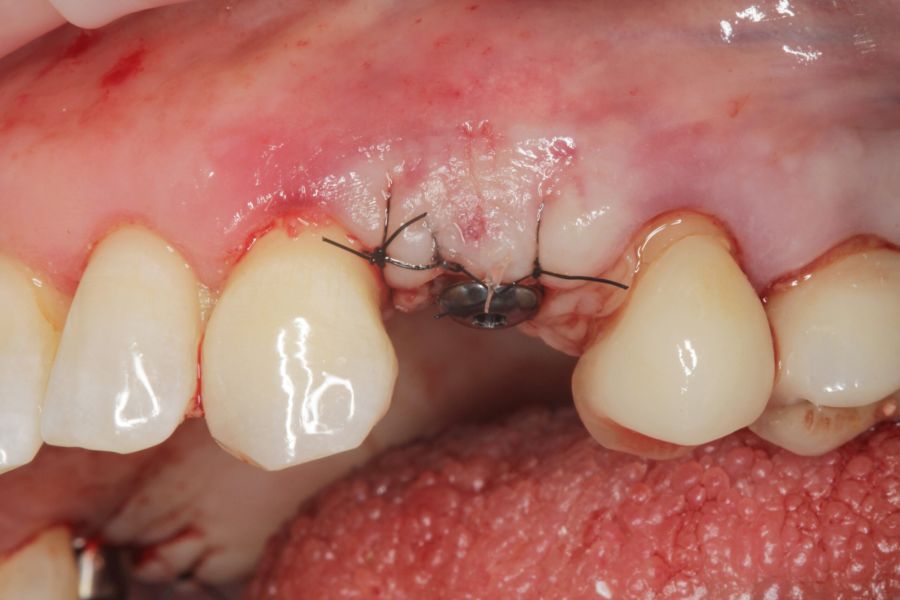

En cuanto a la rehabilitación protésica, en todos los casos se utilizó una prótesis atornillada con transepitelial para prótesis unitaria. La supervivencia de las prótesis fue del 100%, sin encontrarse fracaso en ninguna de ellas al igual que los implantes, con un tiempo de seguimiento de tres años. Durante el primer año, en las visitas de control, ninguno de los implantes mostró sangrado al sondaje ni inflamación de los tejidos periimplantarios. La media de la pérdida ósea en este punto fue de 0,32 mm (+/- 0,60) y la media de la pérdida ósea distal de 0,31 (+/- 0,48). A los dos años, no se registraron tampoco signos inflamatorios en ninguno de los implantes y la pérdida ósea mesial del conjunto fue de media de 0,38 mm (+- 0,54) y la distal de 0,64 mm (+/- 0,70). En la última visita a los 3 años, los tejidos periimplantarios siguieron estables, sin signos de inflamación y la media de la pérdida ósea mesial fue de 0,40 mm (+/- 0,53) y la distal de 0,69 (+/- 0,55) (Figura 5). En las Figuras 6-12 se muestra uno de los casos incluidos en el estudio.